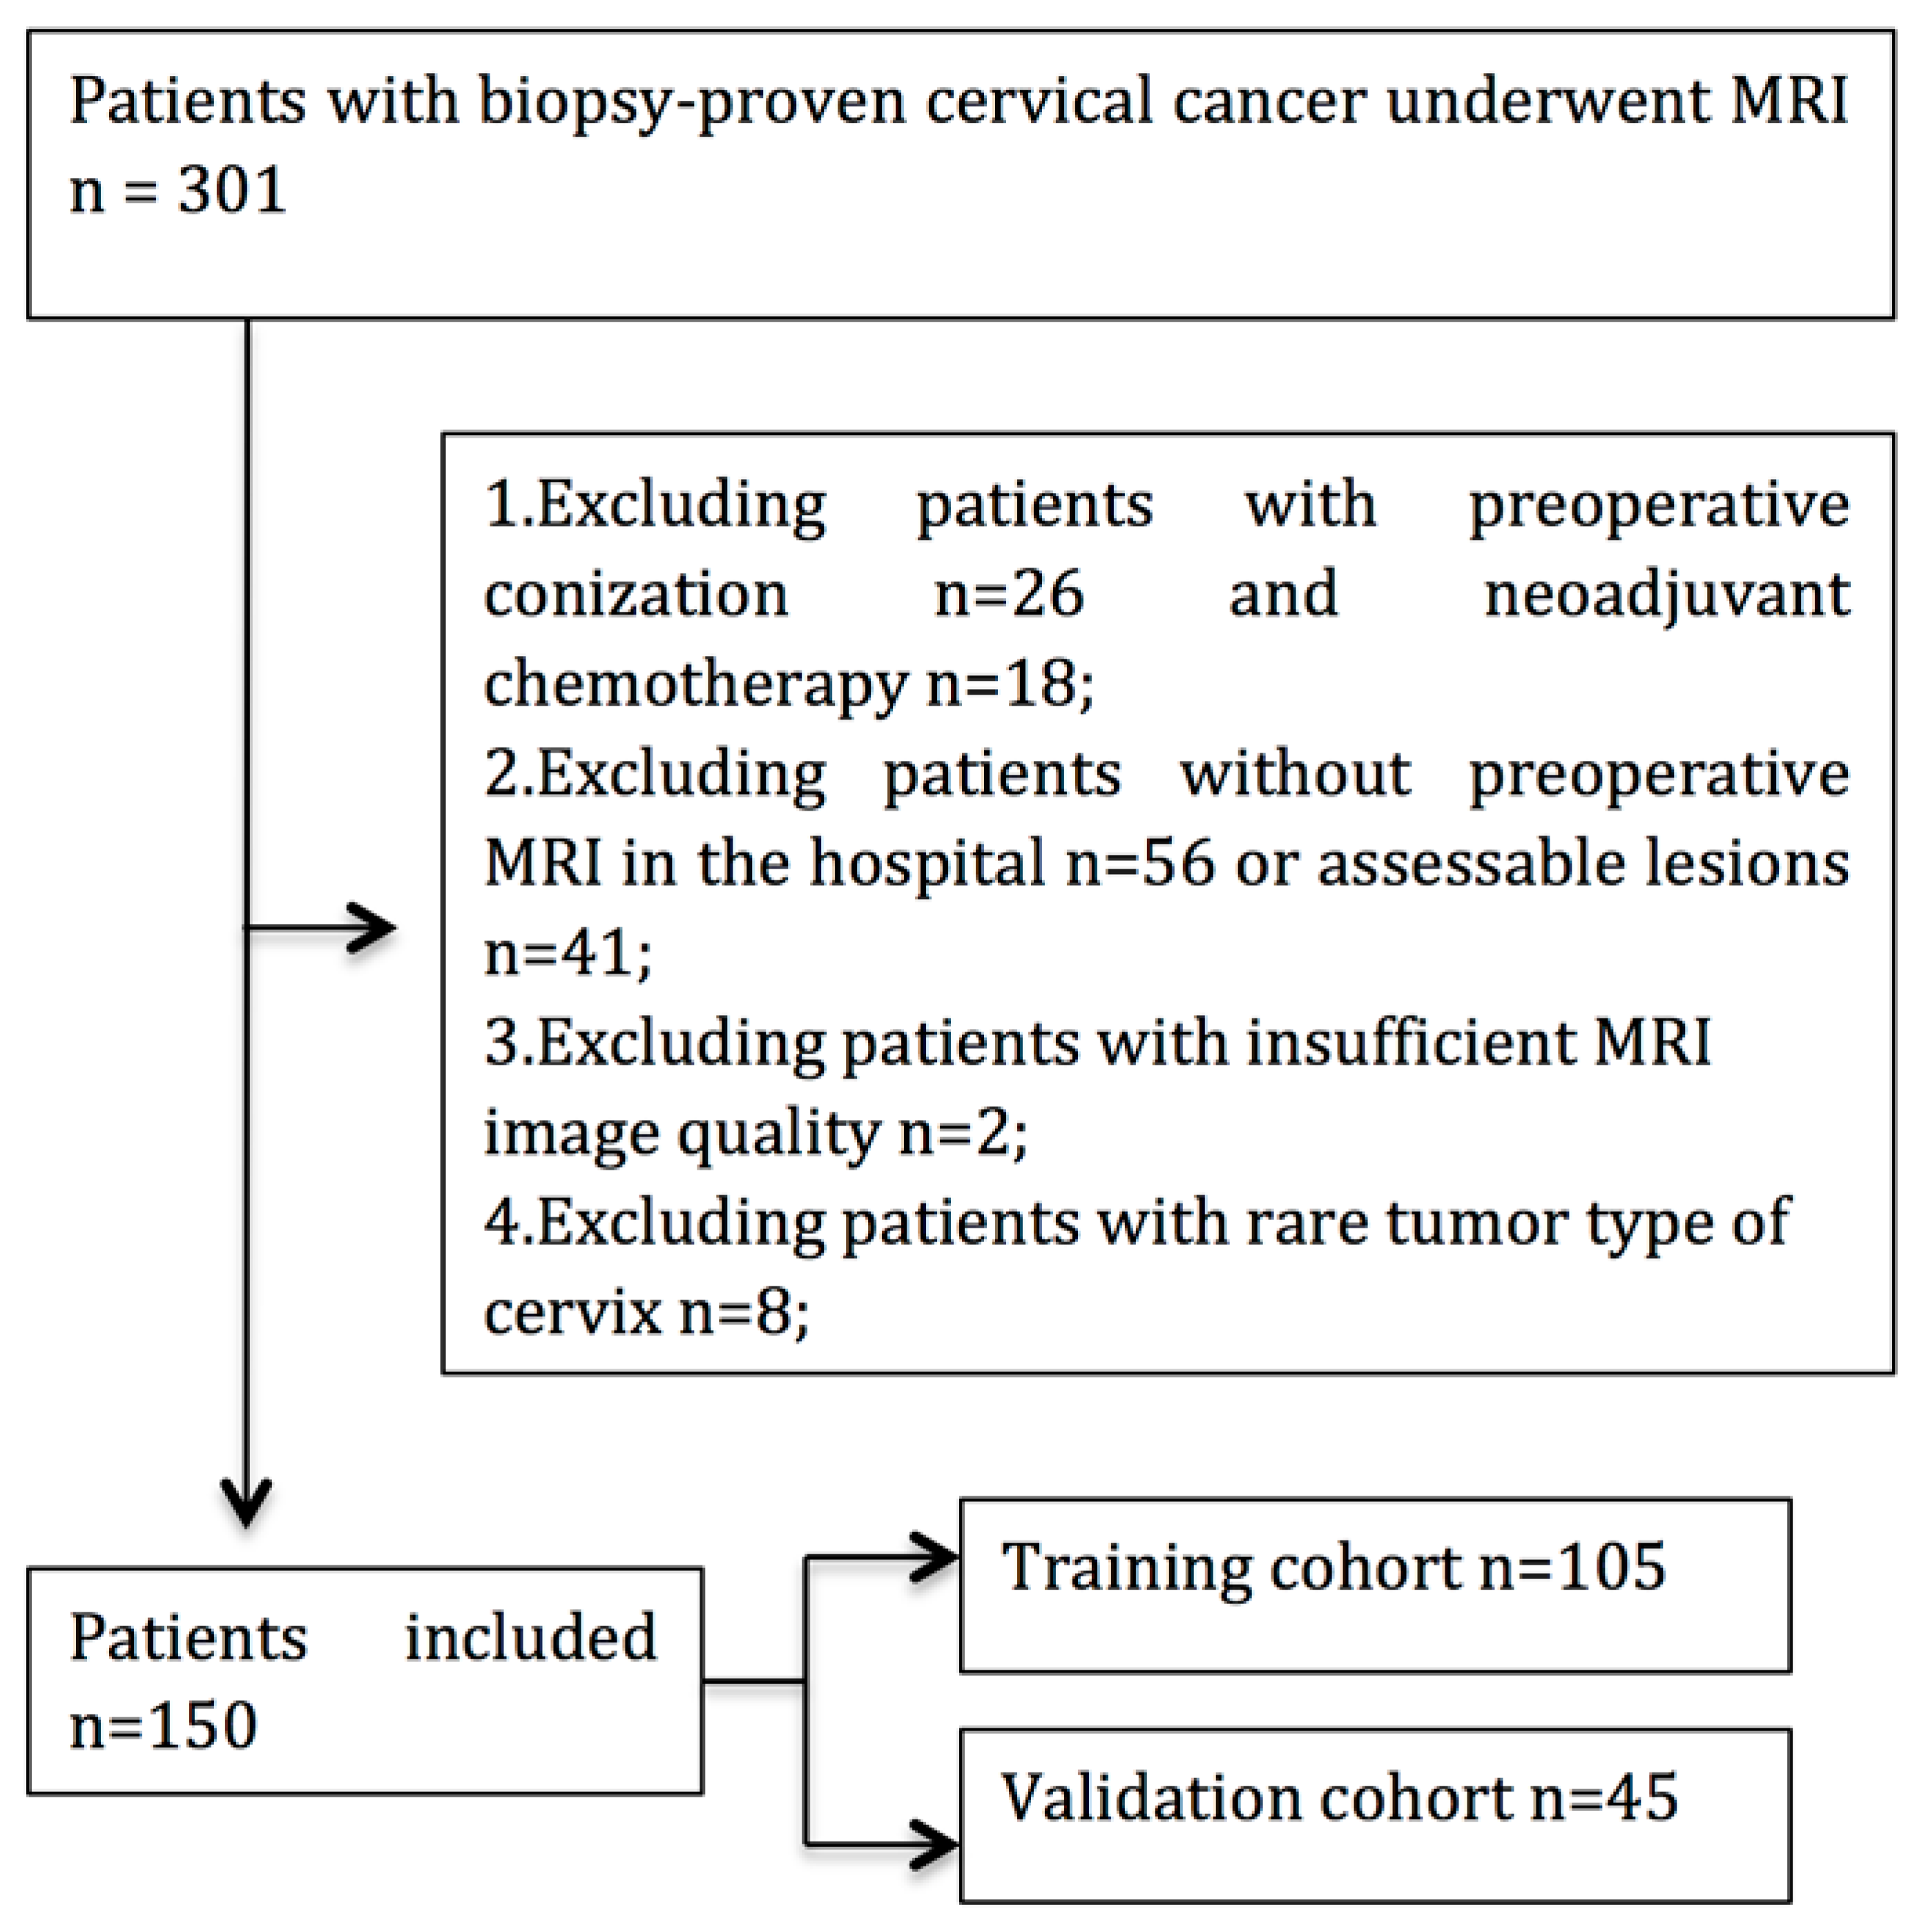

2.1. Patient

3.1. Patients’ Clinicopathologic Characteristics